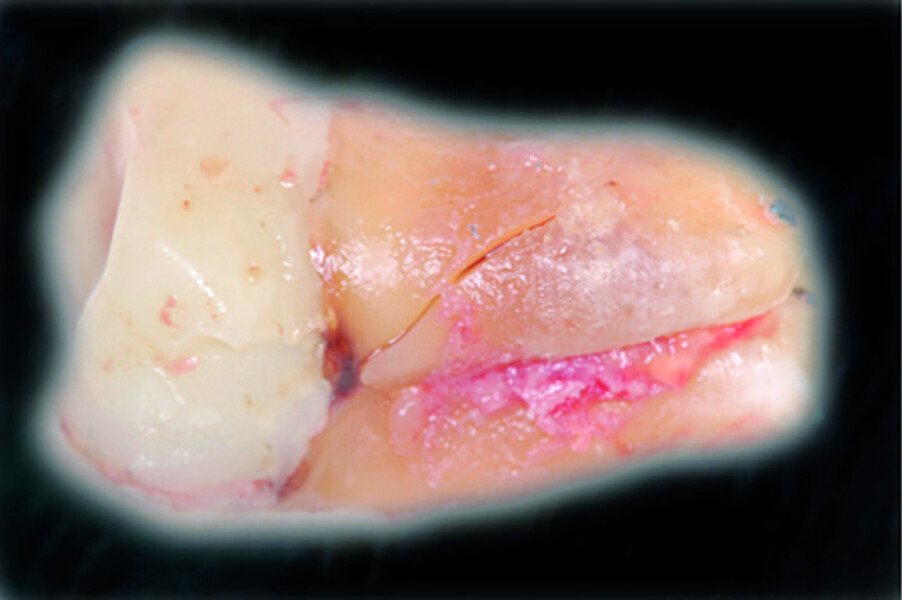

Fig. 12: Pulp chamber floor perforation, immediately after extraction.